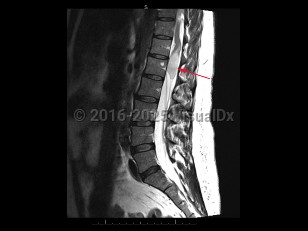

Cauda equina syndrome

Onset is typically gradual but can be acute. Signs and symptoms include severe back pain that may radiate into one or both legs, saddle anesthesia, leg weakness or paraplegia, urinary or bowel dysfunction, sexual dysfunction, and gait disturbance. There may be reduced or absent patellar, Achilles, anal, and bulbocavernosus reflexes.